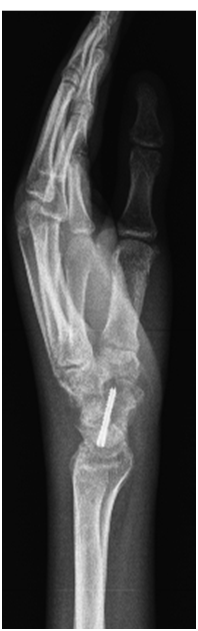

A 23-year-old male patient who was suffering from severe pain and limitation of movement on the left hand and wrist presented to our clinic. The patient’s complains were started 18 months ago. After surgical intervention for avascular necrosis 45 days ago he used casting for 30 days. After surgery the pain has turned out to be more severe and burning. On the physical examination, there was nearly complete limited range of motion on the entire movements of the left wrist, metocarpophalangeal, proximal interphalangeal, and distal interphalangeal joints. Furthermore, especially dorsal redness, thin, shiny, moist skin, increased heat and increased hair on the left hand was detected (Figure 1). There was patchy osteopaenia particularly in the peri-articular regions (Figure 2). With the diagnosis of complex regional pain syndrome type-1 calcium 1000 mg / day, cholecalciferol 800 IU/day, naproxen sodium 750 mg / day and gabapentin 1800 mg / day was started. A rehabilitation program was started including TENS, contrast bath, electrical stimulation and exercise program. After 4 weeks of treatment, the patient's pain was completely reduced. Wrist and other hand joint movements were completely turned out to be normal (Figure 3). Written consent of the patient has been obtained.

Figure 2 Patchy osteopaenia.